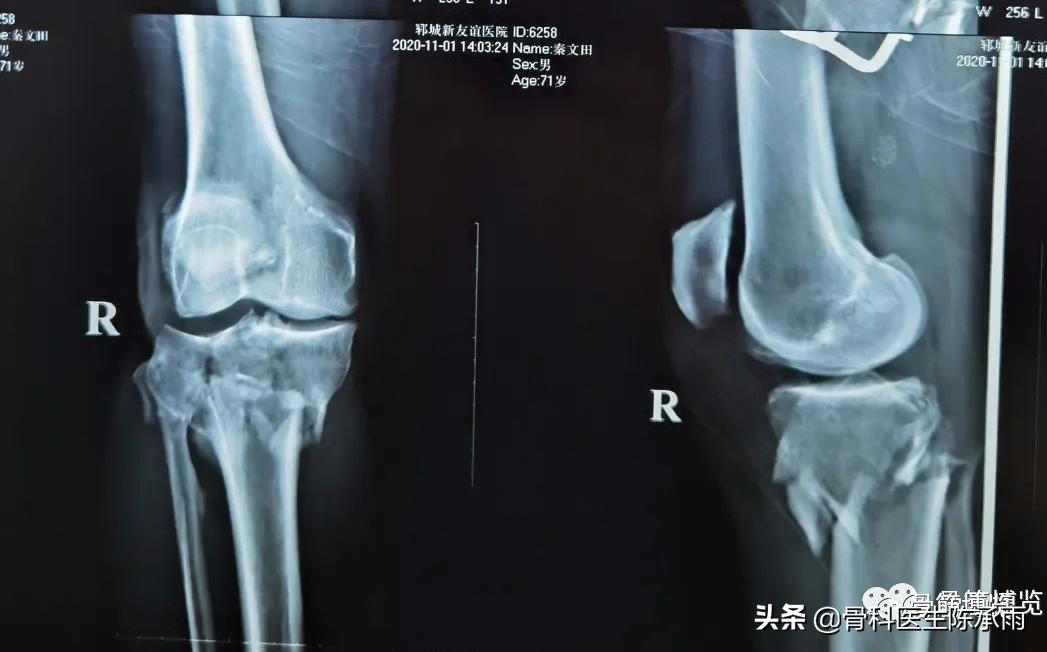

下例胫平台骨折皮肤条件差,内侧板取两端小切口置入内板固定。胫骨结节处撕脱骨折以1枚拉力螺钉固定。